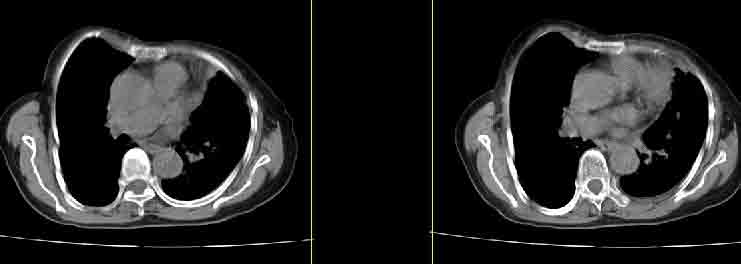

女77岁因左侧胸痛伴咳嗽入院;提示:病灶平扫45hu,强化145hu补充:双肺内未闻及干湿罗音

定位肺内,强化显著(100hu以上),考虑感染性病变先,抗炎后复查排除占位。

我的诊断意见:左肺上叶前段肺癌伴节段性不张。

在不张的肺内见到不规则的软组织,而且强化是不均匀的(该点可能是我的图像作得不好的原因)。

强化大于60hu多考虑炎性病变

左上肺前段可见分叶团块影,强化明显,周围见带状不张影,右肺结节,左肺沿肺纹模糊片状影,考虑左上肺占位,肺癌可能性大。